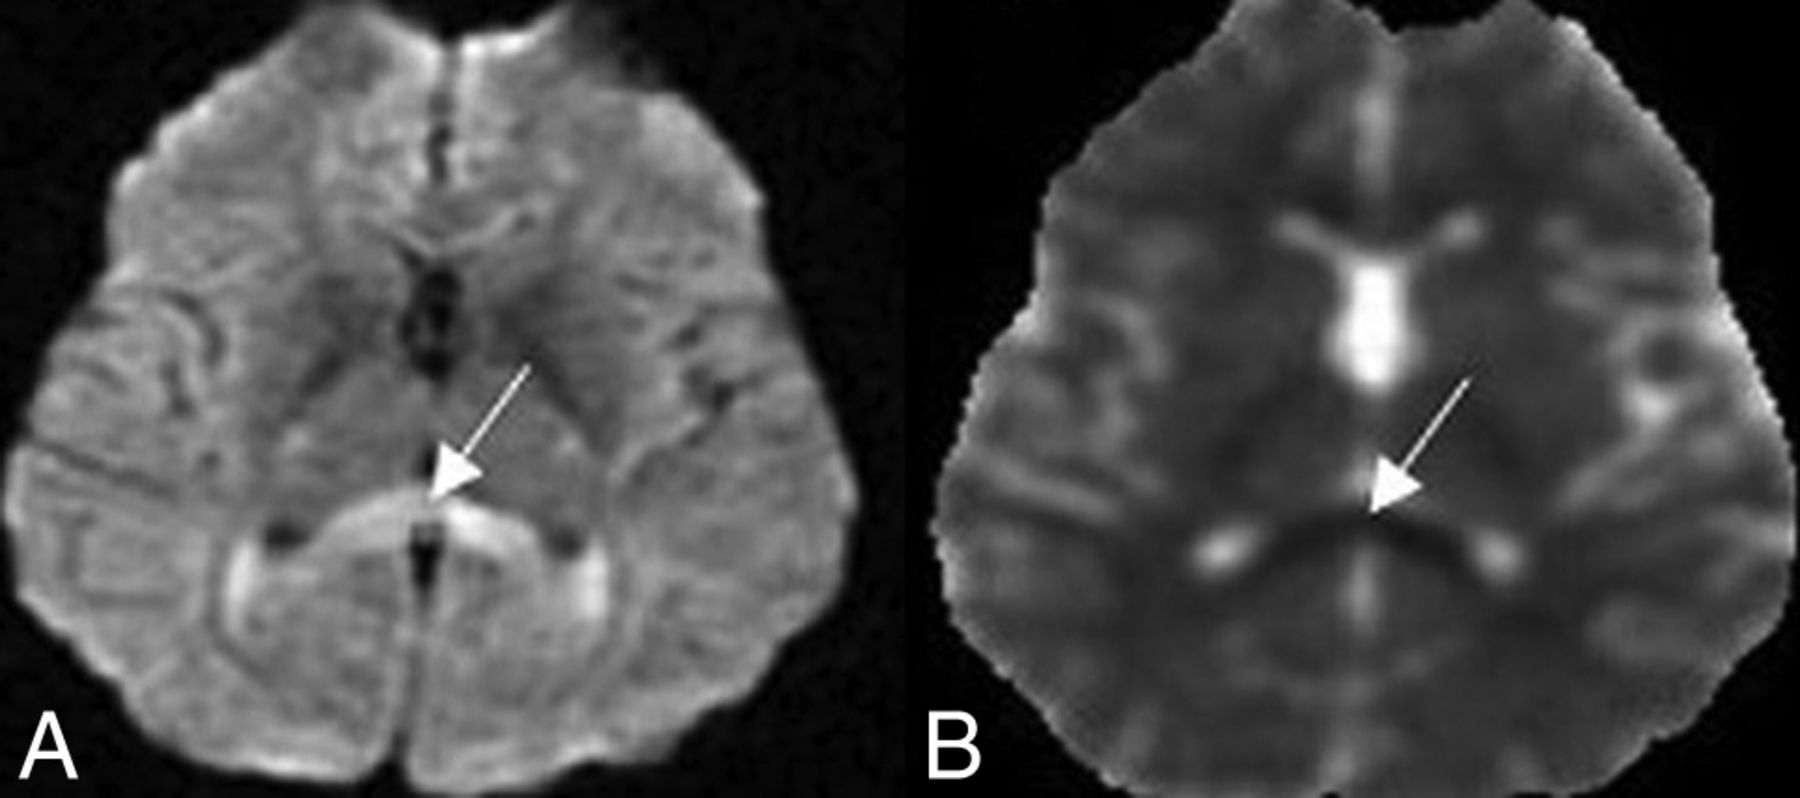

Prominent perivascular spaces were noted in 4 patients (15.3%), ranging from type 1 to type 3 (Fig 5). Diffusion restriction involving the splenium of the corpus callosum was noted in 2 patients (Fig. 6). One patient had multiple subcortical diffusion restrictions.

Axial T2 images show type I (A) and type III (B) prominent perivascular spaces.

Axial DWI (A) and ADC map (B) sequences show diffusion restriction involving the splenium of corpus callosum.